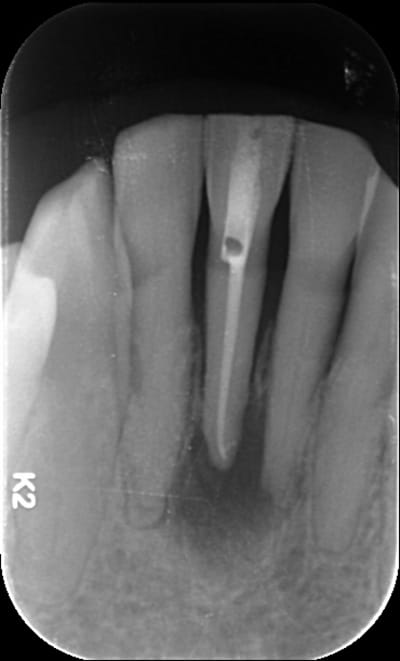

Elle a un second canal lingual ta 31

+1 pour 2 canaux

La saloperie... Pourtant cliniquement j'ai rien trouvé. Je vais retenter avant de prendre le davier. Et pour les morceaux de "racines" en apical de 41 et 32 vous pensez quoi?

Apex fracturés?

D'ailleurs, c'est une 41.

Je pense que j'ai compris, je pense que tu devrais trouver le second en linguo distal.

Pour les apexs (?), la lésion ne semble pas centrée dessus. Si résection, peut-être devras tu alors les virer et faire 2 endos supplémentaires...

Recherche ce canal supplémentaire avant. (disto lingual!)

A la base je pense qu'il y avait un second canal en lingual. Regarde les coupes horizontales tu devrais le trouver ou au moins l'imaginer. Sur les coupes sagittales, le canal que tu as obture est deporte en vestibulaire, c'est une bonne indication. Sur la retro tu vois bien les deux racines de l'incisive latérale, tu trouves en general 2 canaux sur la centrale dans ce cas la.

Je vois de plus en plus souvent des incisives et canines mandibulaires avec 2 racines (encore une 33 traitée il y a 15 jours avec 2 racines chez une dame de 82 ans, chez qui j'ai précédemment retraitées les 42 et 32 à 2 racines avec infection apicale aujourd'hui totalement rentrés dans l'ordre).

Donc les dents de ta mamie ont 2 racines et 2 canaux et avant de sortir ton davier prend en compte l'état physique et mental de cette dame ainsi que la maintenance de son hygiène dentaire !!